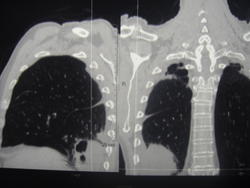

Больной лечился у невролога, провели проф ФГ- выявили деструктивную пневмонию, пролечилили, на Р контроле- ухудшение, клиники абсцесса не было, была боль в гр клетке спереди справа. Из анамнеза- лечился оперативно 6-7 лет назад по поводу рака верхней губы, в ООД не наблюдался последние годы. Данные за туб этиологию сомнительны, как мне кажется, очагов отсева по слоям не вижу,  хотя мож не так смотрю. Ваше мнение коллеги, абсцесс это или нет?

По опыту хочу сказать, что в настоящее время классической клиники абсцесса можете и не увидеть. Очень она изменилась. В данном случае контроль  должен помочь. В связи с тем, что стенки имеют разную толщину и вокруг почти нет изменений, больше склоняюсь к полостной форме рака.

Спасибо, на послойных просмотрах тоже не увидела никаких отсевов. Хотя туб и онко отсевы ничем не отличались бы, да? Но СКТ должно и их отдифференцировать, чтобы больного направить на лечение по профилю.